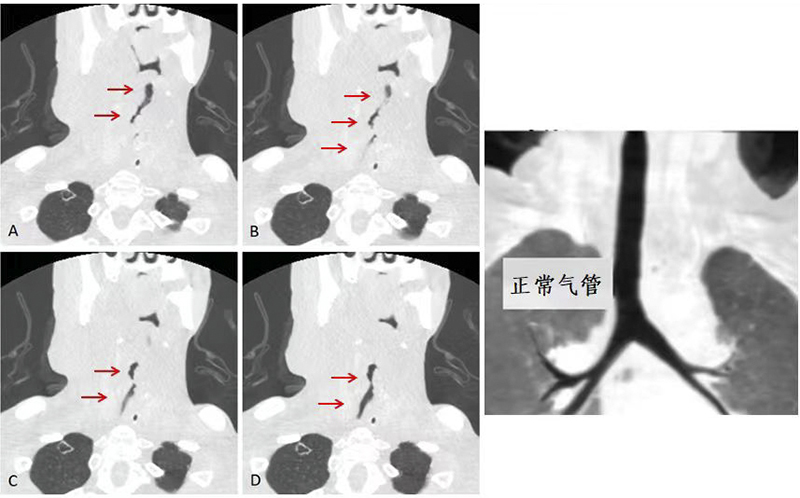

日前,广先生(化名)因呼吸困难到柳州市人民医院耳鼻咽喉科就诊,入院时患者颈部肿胀明显,可触及肿块。医生进一步询问病史了解到广先生既往有喉肿瘤病史,已治疗多年;现由于颈部肿物过大,导致患者气道受压影响呼吸,随时可能窒息危及生命。

入院完善颈部CT后提示喉癌术后复发及综合治疗后改变,肿物较前增大,合并感染。同时局部肿瘤侵犯气管,目前梗阻的气道随时可能危及患者生命,立即建立人工气道才有可能缓解呼吸困难、挽救生命并且提高患者的生存质量。但患者目前的基础状况要经历麻醉、建立人工气道手术,将可能出现插管困难、气道出血、甚至突发心脏骤停等情况。面对患者复杂的病情及棘手的治疗,患者及家属仍然表达了强烈的生存意愿,希望尽量延长生命,并且能最大程度地提高患者的生存质量。